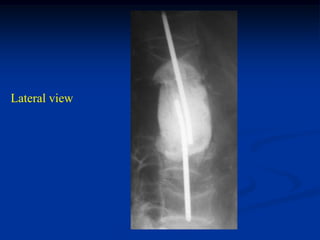

Case #221

82 year male with chordoma lower sacrum

Lateral view

Sagittal T-1 MRI

Sagittal T-2 MRI

tumor

Axial T-1 MRI